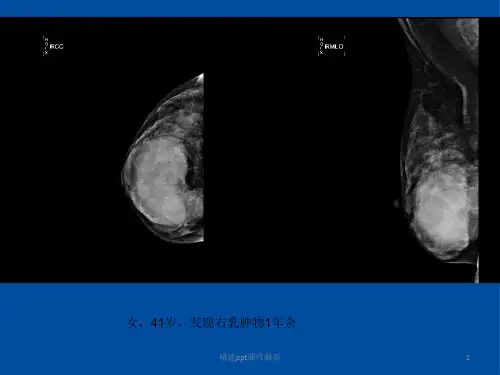

常见,而浸润性导管癌少见